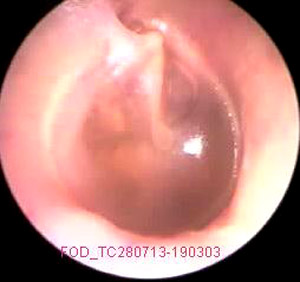

JFC Otitis media serosa de origen disbárico.